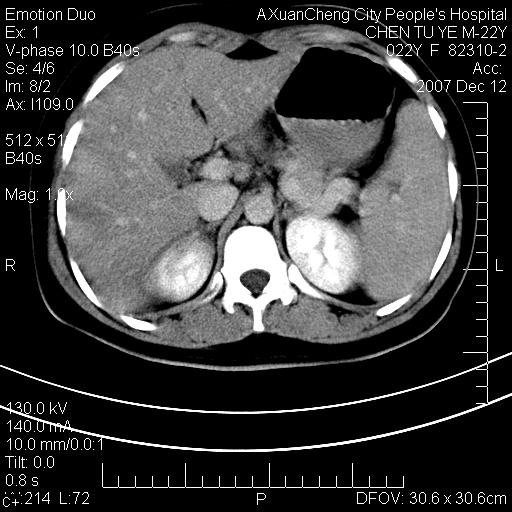

超声提示肝右前叶占位,约2.5cm.

各位战友看看病灶在什么地方,可是右前叶进肝裂部低密度影,平扫ct值约10以下,增强后增高明显

1 脾大,慢性肝损伤. 2 肝脏脂肪侵润.  3 你所指的部位疑点,我没看出有问题.

脂肪肝.楼主所指部位不考虑异常,为肝圆韧带影.

1 脾大,慢性肝损伤. 2 肝脏脂肪侵润.

脂肪肝,脾大

重度脂肪肝.

不均匀脂肪浸润,版主所说的病灶为肝园韧带服着点。

考虑肝圆韧带。